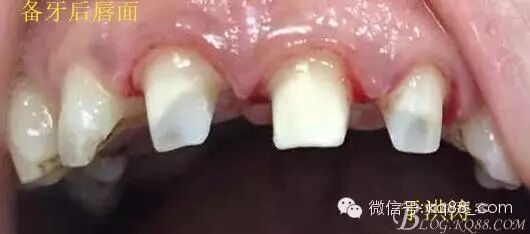

檢查:明顯可見22牙冠橫向斷裂至頸1/3處,近遠中與腭側斷裂至齦下??梢?/span>11牙冠斜向近中斷裂,近中與腭側均斷裂至齦下。21牙冠中1/3有裂痕。11 21 22松動(0),11 21叩(+),22叩(-),11 21 22探(-),11 21 22冷熱(-)。11 21 22唇側牙齦與粘膜和根尖相應部位未見明顯改變。11 22腭側牙齦增生性改變。11 21 22腭側粘膜和根尖相應部位未見改變。11 21 22舌側窩均有充填物。面部左右對稱無改變。余牙正常。(11,21,22牙冠顏色無改變)。 輔助檢查:X線片檢查11 22牙冠均有缺失。11 21 22 髓腔內均有充填物,11充填不到位, 21充填不實,22充填到位髓腔高密度影像。11 21 牙周膜有增寬,21根尖區(qū)有2mm左右低密度影像。未發(fā)現(xiàn)有牙根側穿或斷裂異物。 診斷:11,21慢性尖周炎,11,22殘冠。 治療計劃: 22無需治療。11 21 建議牙齒根管再治療。告知情況及費用。 1,11 21去除根充物。 2,11 21根管治療。 3,11 22纖維樁樹脂核修復。 4,高頻電刀去除11 22腭側牙齦組織到斷面。 5,11,21,22全瓷單冠修復牙齒。 治療過程:經(jīng)患者同意。H銼去除11 21原有充填物,未發(fā)現(xiàn)明顯滲出物,無異味。K銼疏通根管,VDW根測儀測量長度,11牙20mmWL,21牙20mmWL。S3鎳鈦器械預備根管。(全程1%次氯酸鈉沖洗EDTA溶解潤滑)試尖片顯示牙膠未到位,繼續(xù)向牙根尖各2mm進入預備。吸潮紙尖吸干根管,登士柏樹脂根充糊劑輸送至根尖部位,以測量數(shù)據(jù)用牙膠尖冷充側壓充填根管,3M玻璃離子封閉根管口。不可用患牙啃咬硬物,擇日冠修復。 輔助檢查:插針X線片顯示根管內充填物已經(jīng)取出。試尖片顯示牙膠尖未到位,繼續(xù)用K銼和機括向根尖預備。根充結束片顯示根充密實,無超充,無欠充。 醫(yī)囑:常規(guī)醫(yī)囑,不適隨診。 各步驟操作見下圖 于洪濤 2015.02.03 復 診 主訴:無疼痛,不適癥狀已經(jīng)消失。 檢查:11 21 充填物存在邊緣封閉完好,叩(-)松動(0)牙齦及周圍同初診。11 21 22無任何不適。 治療過程:由于患者自身原因即將兩個月來復診。拍X線片,去除11 22髓腔內部分牙膠,P鉆預備根管到達預定位置。粘結纖維樁,制作冠核。初預備11 21 22牙冠。高頻電刀按廠家要求功率和方法去除11 22腭側牙齦組織到達牙齒斷裂部位,調整檔位和功率繼續(xù)凝固和精修腭側組織,11 21 22排齦精修拋光。硅橡膠兩次法取模,可見模型完整肩臺清晰。制作臨時冠,科爾不含丁香油臨時冠粘結系統(tǒng)粘接。 模型送技師制作。預約義齒佩戴時間。(需術前牙齒比色) 輔助檢查:X線片顯示根尖低密度影像消失,牙周未見異常。X線片顯示纖維樁密合到位。 醫(yī)囑:不可用臨時牙肯咬硬物,不適隨診。 各步驟操作見下圖 于洪濤 2015.03.26 復 診 主訴:牙齒無癥狀,自感腭側術區(qū)舌舔粘膜不適。 檢查:臨時冠完整,無松動,邊緣緊密。牙齒無疼痛,唇側牙齦無明顯紅腫,腭側牙齦愈合良好,牙冠肩臺邊緣清晰。腭側牙齦術區(qū)中度觸及有少量滲血。 治療過程:義齒制作完成。去除臨時冠及粘結物。義齒試戴調整完全就位,無懸突,無縫隙。清洗義齒,氫氟酸處理義齒50秒(加強醫(yī)患防護),沖洗吹干,偶聯(lián)劑處理備用。基牙37%酸處理15秒,沖洗吹干,隔濕,排齦,涂第五代粘結劑。小蜜蜂雙固化樹脂水門汀激活攪拌注入義齒中,按順序就位,加壓力,牙線去除牙縫隙多余樹脂,涂阻氧劑,基牙唇腭側各光照固化3秒之后去除多余水門汀取出排齦線,繼續(xù)光照固化牙齒每個面20秒。精細查找去除多余水門汀。 醫(yī)囑:1,患牙咀嚼硬物加以注意。 2,常規(guī)醫(yī)囑,不適隨診,。 3,加強口腔衛(wèi)生意識。定期復診檢查。 各步驟操作見下圖 于洪濤 2015.04.07 回訪病例 主訴:咀嚼食物非常自如,無任何不適。 檢查:義齒牙體完整。無松動,無叩痛。唇側牙齦紅潤質韌無萎縮,腭側術區(qū)牙齦愈合良好,無炎癥改變。唇腭側根尖相應部組織無改變。余牙正常。 輔助檢查:X線片顯示牙根及周圍未見異常。未見骨萎縮。牙冠及頸部未見異常。 醫(yī)囑:定期檢查義齒,不適隨診。 各步驟操作見下圖 于洪濤2015.04.28